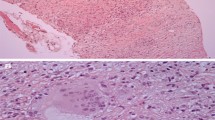

Sarcoidosis is a multisystem granulomatous disease of unknown etiology, with early descriptions dating back to 1869 [1]. Current pathophysiology models propose an aberrant immune reaction to an unknown antigen in genetically susceptible hosts [2, 3]. Sarcoidosis has a lifetime prevalence of 4 to 40/100,000 in whites and up to three times that in other racial groups such as African-Americans [4]. Sarcoidosis can affect any organ system but most commonly affects the lymph nodes and lungs and is non-life-threatening. Non-caseating, non-necrotic granulomas are the histological hallmark; however, chronic disease may lead to fibrosis.

Unlike systemic or pulmonary sarcoidosis, cardiac sarcoidosis (CS) may present acutely and is associated with a poorer prognosis and higher mortality, largely related to the increased risk of sudden cardiac death [5]. In addition, it is a highly under-recognized entity. While studies suggest CS is diagnosed in 2 to 7% of patients with sarcoidosis [6], autopsy studies demonstrate cardiac involvement in up to 25% [7, 8], with more than half clinically occult at time of death [4, 9]. Imaging studies aimed at detecting asymptomatic CS in patients with sarcoidosis suggest involvement in up to 55% (summarized in [10]). An accurate estimate of CS prevalence is unclear due to a lack of standardized diagnostic criteria. Ethnic variation exists, with CS evident in 68% of Japanese but 14% of white patients with sarcoidosis [11, 12]. Sarcoid granulomas are most frequently detected in the myocardium but can also occur in the endocardium and pericardium. Commonly effected areas include the basal ventricular septum, left ventricular (LV) free wall, papillary muscles, and right ventricle [6]. Importantly, CS accounts for a significant proportion (10 to 25%) of sarcoid deaths in the US population [9] and even higher (50%) in Japanese populations [7, 11] highlighting the need for early detection and intervention [6].